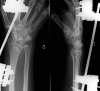

Figure 2.

AP and lateral radiographs of a patient operated using closed reduction and external fixation.